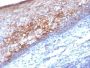

Applikationen IHC

IHC, FFPE (verified)

Positive Control

A-375, HUV-EC or HeLa Cells. Tonsil or Melanoma.

Melanoma

Higher concentration may be required for direct detection using primary antibody conjugates than for indirect detection with secondary antibody|Immunohistology (formalin)|Staining of formalin-fixed tissues requires boiling tissue sections in 10 mM Tris with 1 mM EDTA, pH 9.0, for 10-20 min followed by cooling at RT for 20 minutes|Flow Cytometry 0.5-1 ug/million cells/0.1 mL|Immunofluorescence 0.5-1.0 ug/mL|Optimal dilution for a specific application should be determined by user